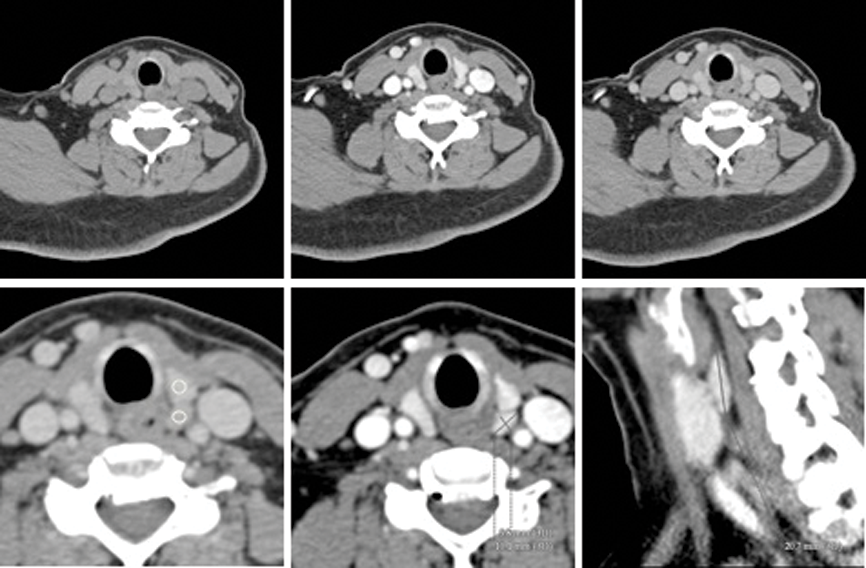

Surgical challenges in advanced or recurrent thyroid malignancy

The management of thyroid malignancy and extent of surgery is controversial, especially considering the limitations of preoperative diagnosis. Neil Tolley provides guidance and reminds us of our responsibility not to over-treat. In the UK, 16% of thyroidectomies are performed for...